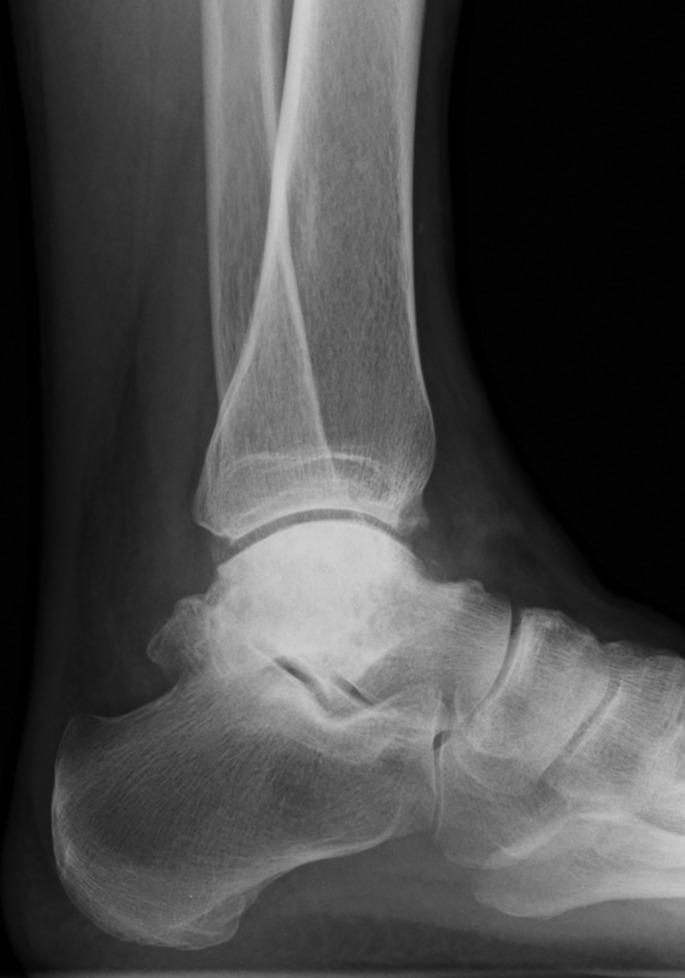

Avascular necrosis tends to occur in the talus because of poor blood supply caused by the extended coverage to the articular cartilage on its surface. Treatment is conservative in the earlier stage of this disease; however, surgical treatment is usually indicated in the advanced stage. Nonunion, leg length discrepancy, or hindfoot instability may occur in patients treated with ankle or tibio-talo-calcaneal fusion. Arthroplasty using a customized total talar prosthesis designed using the computed tomography image of contralateral talus has the potential advantages of weightbearing in the earlier postoperative phase, prevention of lower extremity discrepancy, and maintenance of joint function.